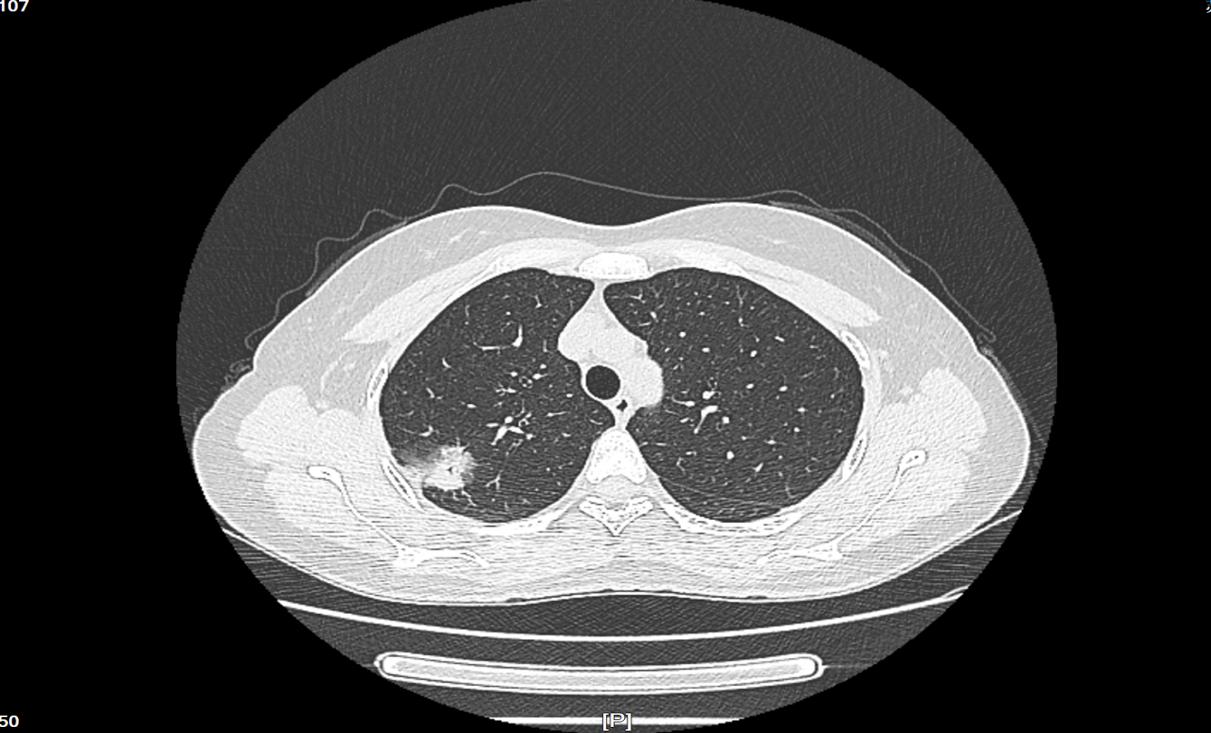

43岁的张女士,每年参加公司常规体检,包括胸部X光摄片等项目,均无任何异常。今年,张女士至我院健康管理中心进行年度体检,其中包括查胸部高分辨平扫CT这一检查项目。7月7日张女士的胸部CT报告为:右肺上叶尖段见一团块状磨玻璃实性混合密度结节,边缘不光整,大小约22mm*25mm,考虑为早期肺癌可能。

张女士术后病理显示为直径2cm浸润性腺癌,无淋巴结转移和胸膜累及。属于早期肺癌(Ia期),及时进行手术干预效果,可达到90%左右的治愈率。